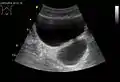

- Divertículos de vejiga como se ve en la ecografía con Doppler[20]

- Divertículos de vejiga vistos en ultrasonido[20]